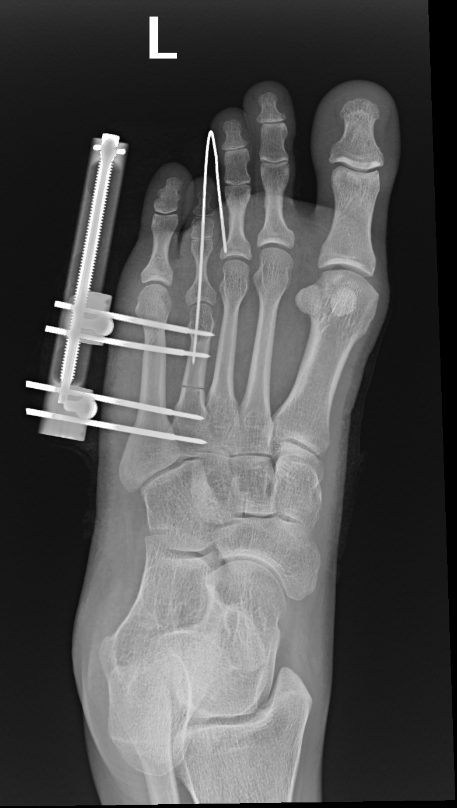

The surgeon in preparation for each surgery preconstructs a customized apparatus. Using wires or pins, the apparatus is surgically attached to the affected limb. Surgery is usually performed percutaneously through small incisions. Special care is taken to minimize injury to the bone and surrounding soft tissue, nerves and blood vessels when making specialized bone cuts.